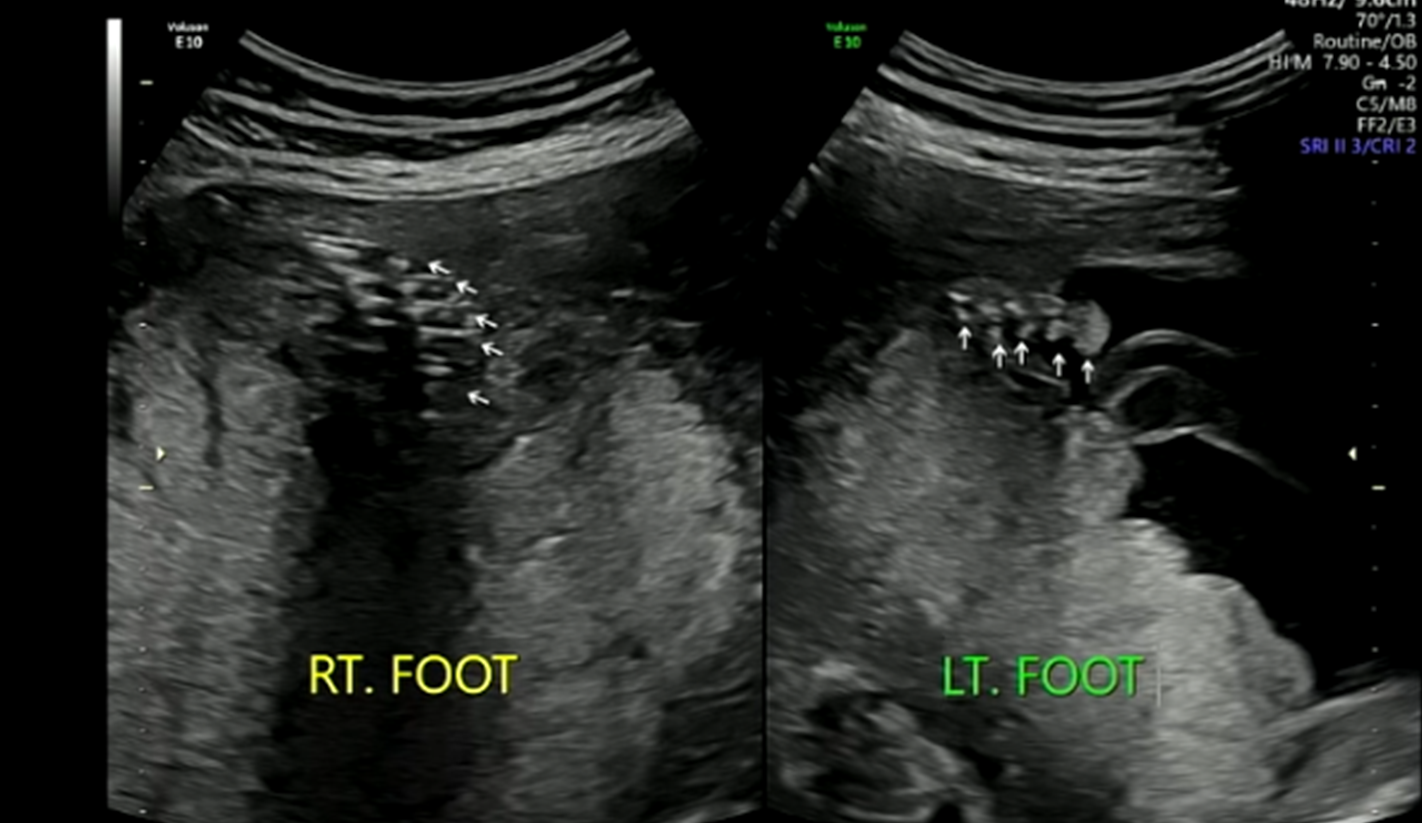

발가락

※ 초음파 용어) RT.FOOT : 오른쪽 발가락 , LT.FOOT : 왼쪽 발가락

발가락도 5개다 있음을 확인하였다.